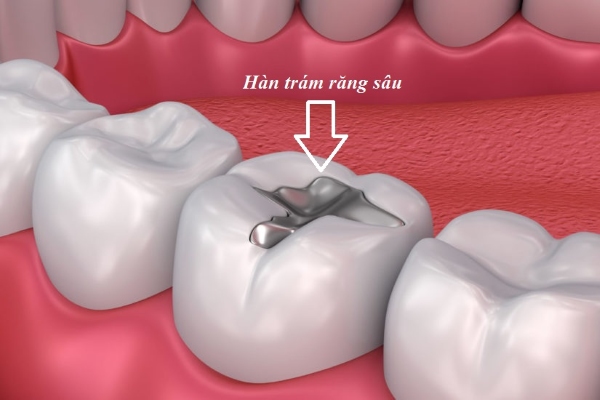

Trám răng tạm thời là phương pháp bảo vệ răng khỏi các tác nhân gây hại như vi khuẩn và mảng bám trong khi chờ đợi điều trị nha khoa chính thức. Nha sĩ sẽ sử dụng chất trám tạm thời để lấp đầy lỗ sâu hoặc phục hồi phần răng bị hỏng, đảm bảo răng được bảo vệ, ngăn ngừa sự phát triển của sâu răng và duy trì chức năng ăn nhai.

Chất trám tạm thời này tạo ra một lớp bảo vệ quan trọng, giúp răng không bị tổn thương thêm và duy trì tính ổn định trong thời gian chờ đợi điều trị tiếp theo. Đồng thời, nó cung cấp sự thoải mái cho bệnh nhân, giúp quá trình điều trị diễn ra thuận lợi và không gây khó chịu.

Miếng trám răng tạm thời thường được làm từ các vật liệu như composite hoặc eugenol, và được sử dụng trong các trường hợp sau:

- Khi có tổn thương do sâu răng hoặc nứt gãy.

Trám răng sâu tạm thời

- Kim loại: Vật liệu kim loại như amalgam hoặc các hợp kim kim loại khác cũng có thể được sử dụng làm trám răng tạm thời. Kim loại có độ bền cao và khả năng chống mài mòn tốt, giúp bảo vệ răng trong thời gian chờ đợi điều trị chính thức.